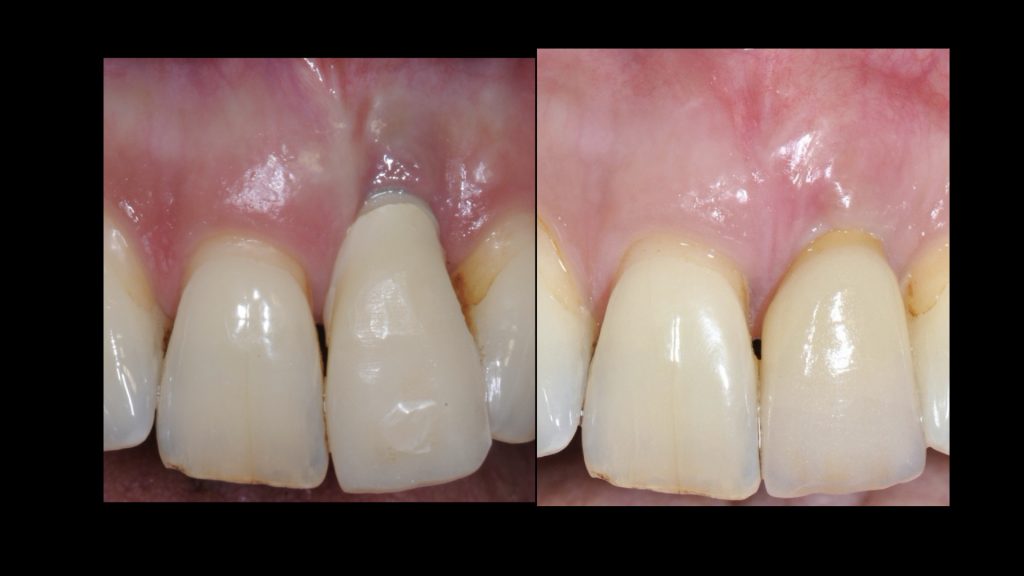

Рис. 9 и 10 после начального заживления временная коронка была адаптирована с помощью композита для тренировки и формирования мягких тканей, аналогично прилегающему правому центральному резцу. Нашей целью также было добиться одинаковой длины 11 и 21 зубов или выровнять высоту десны